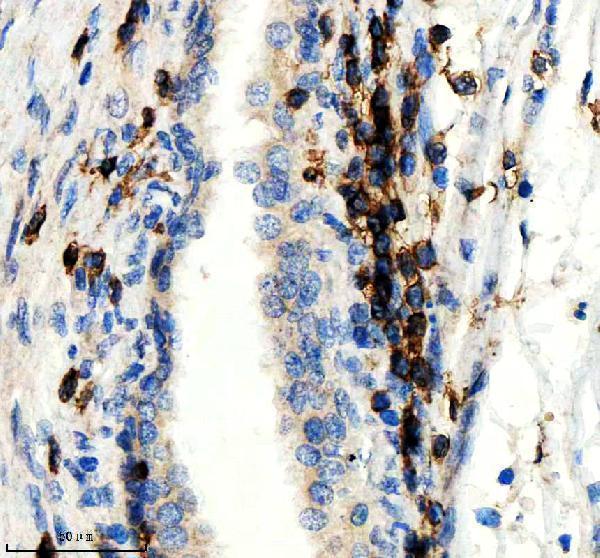

CD3Z is expressed in normal lymphoid tissue and in peripheral blood mononuclear cells (PBMCs) (PubMed:11722641).